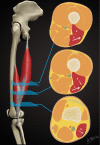

Background: Injury to the distal musculotendinous T junction (DMTJ) of the biceps femoris is a distinct clinical entity that behaves differently from other hamstring injuries due to its complex, multicomponent anatomy and dual innervation. Injury in this region demonstrates a particularly high rate of recurrence, even with prolonged rehabilitation times.

Purpose: To describe the anatomy of the DMTJ of the biceps femoris and analyze the injury patterns seen on magnetic resonance imaging (MRI) to aid prognosis and rehabilitation and minimize the risk of recurrence.

Methods: Acute injury to the DMTJ of the biceps femoris was identified in 106 MRI examinations from 55 patients at a single institution. Each injury was classified as involving the long head, the short head, or both components of the DMTJ, with each component individually graded. Injuries were classified as recurrent if there was a previous MRI demonstrating an acute injury to the DMTJ or if there was scarring present at the site of an acute injury.